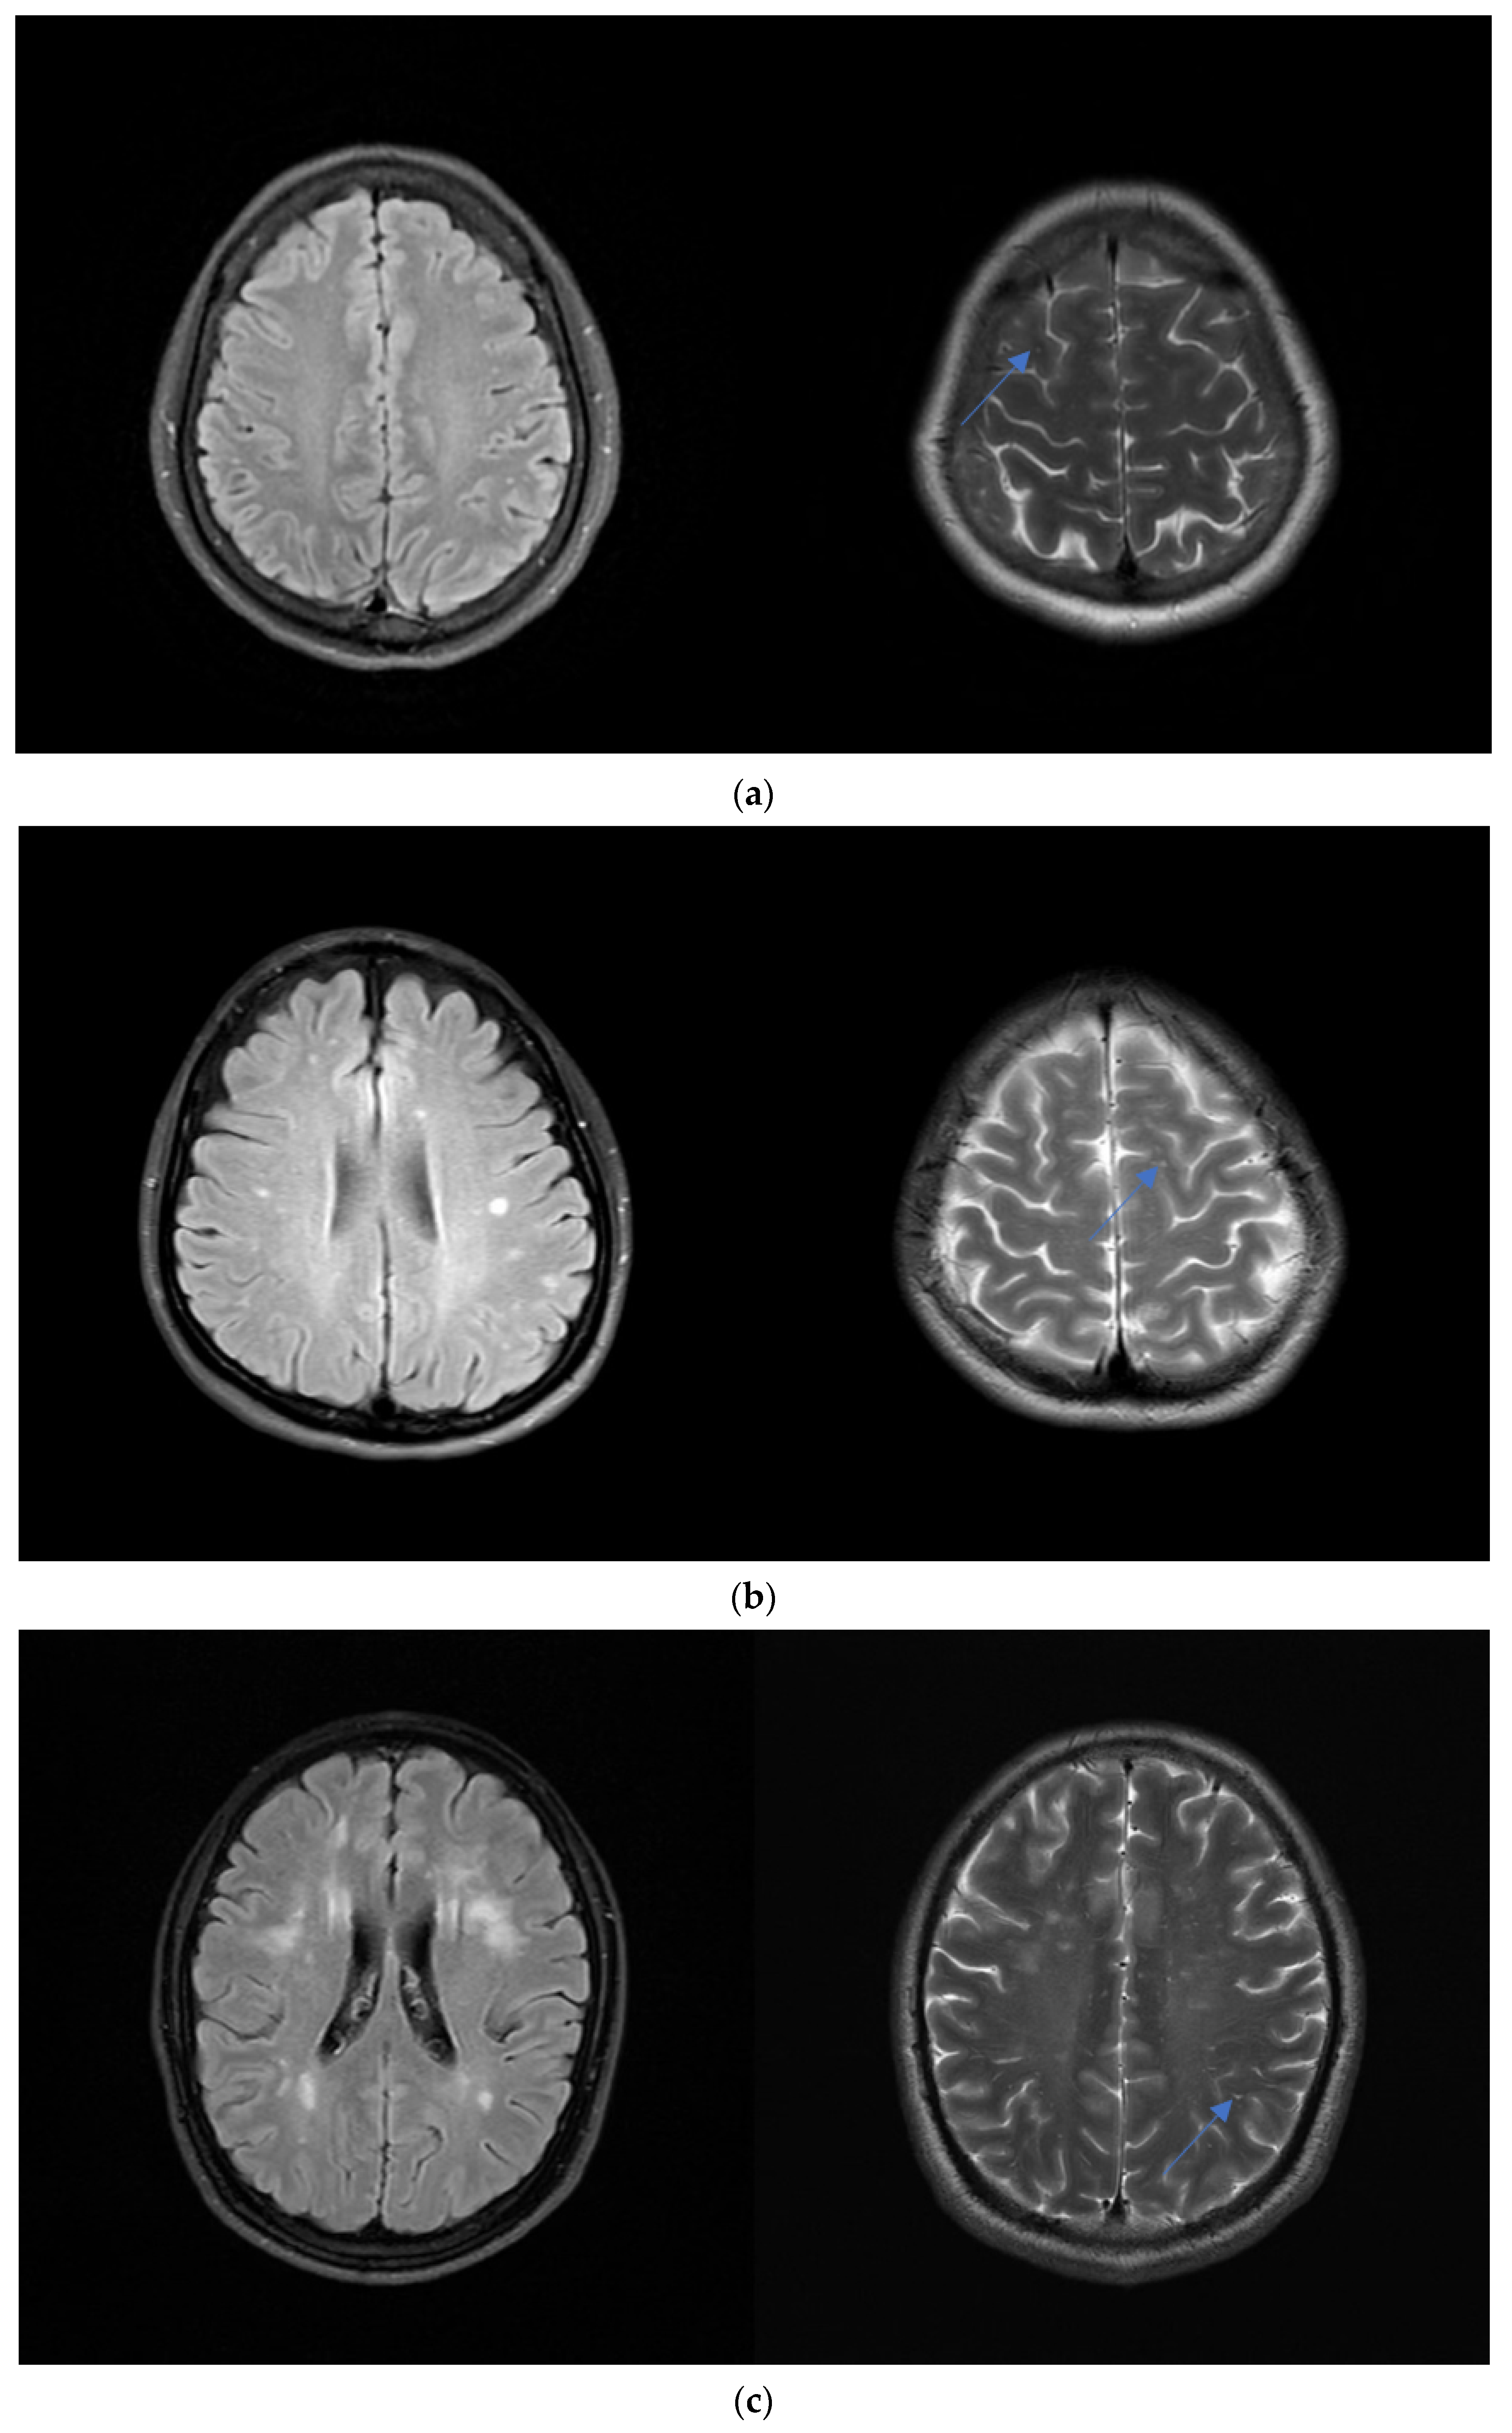

Figure 2.

Levels of the severity of WMH. (a) A 23-year-old woman with a headache. Axial FLAIR MR images show mild DWMH. Axial T2-weighted images show grade 1 CSO-ePVS (blue arrow). (b) A 36-year-old woman with dizziness. Axial FLAIR MR images show moderate DWMH. Axial T2-weighted images show grade 2 CSO-ePVS (blue arrow). (c) A 45-year-old man with visual disturbance. Axial FLAIR MR images show severe DWMH. Axial T2-weighted images show grade 3 CSO-ePVS (blue arrow).